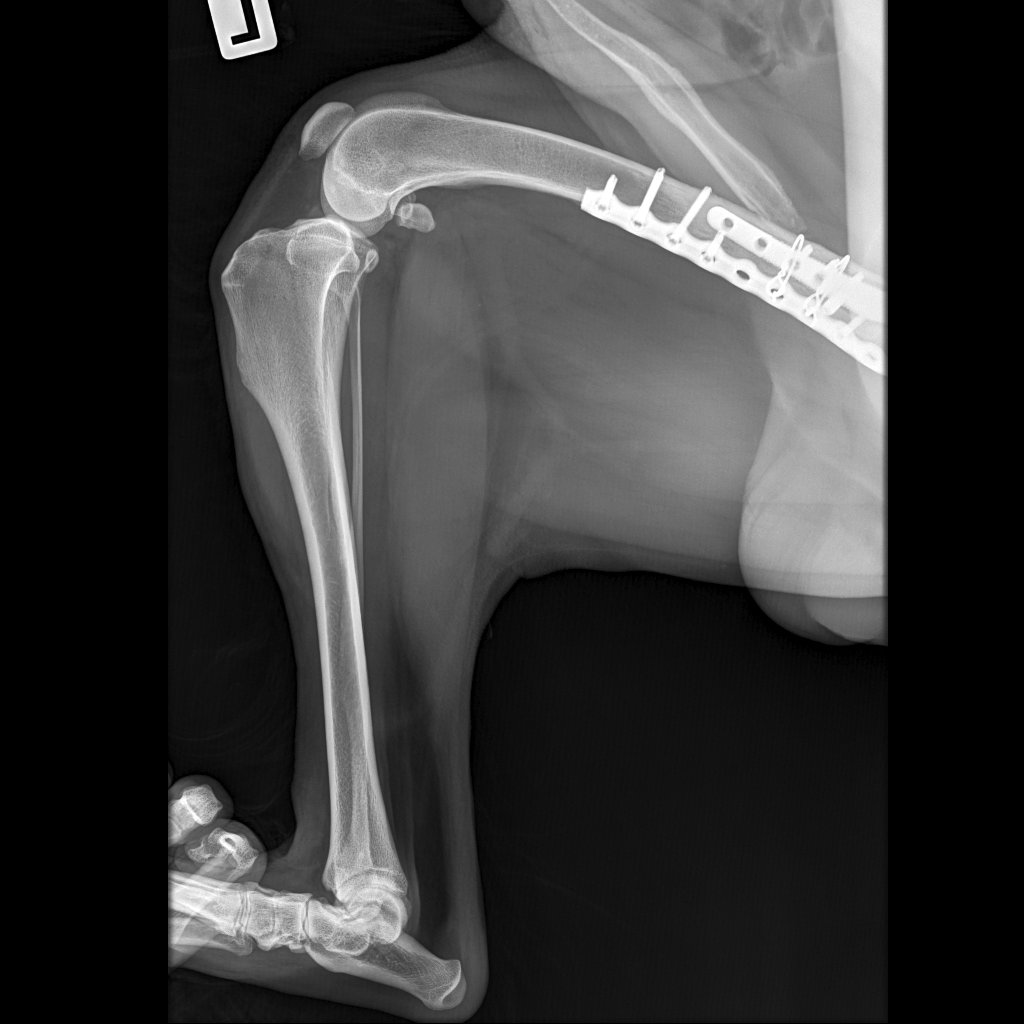

D44D94F0-4FAE-4206-846A-F1875E264EC7.jpeg

19.05.2023